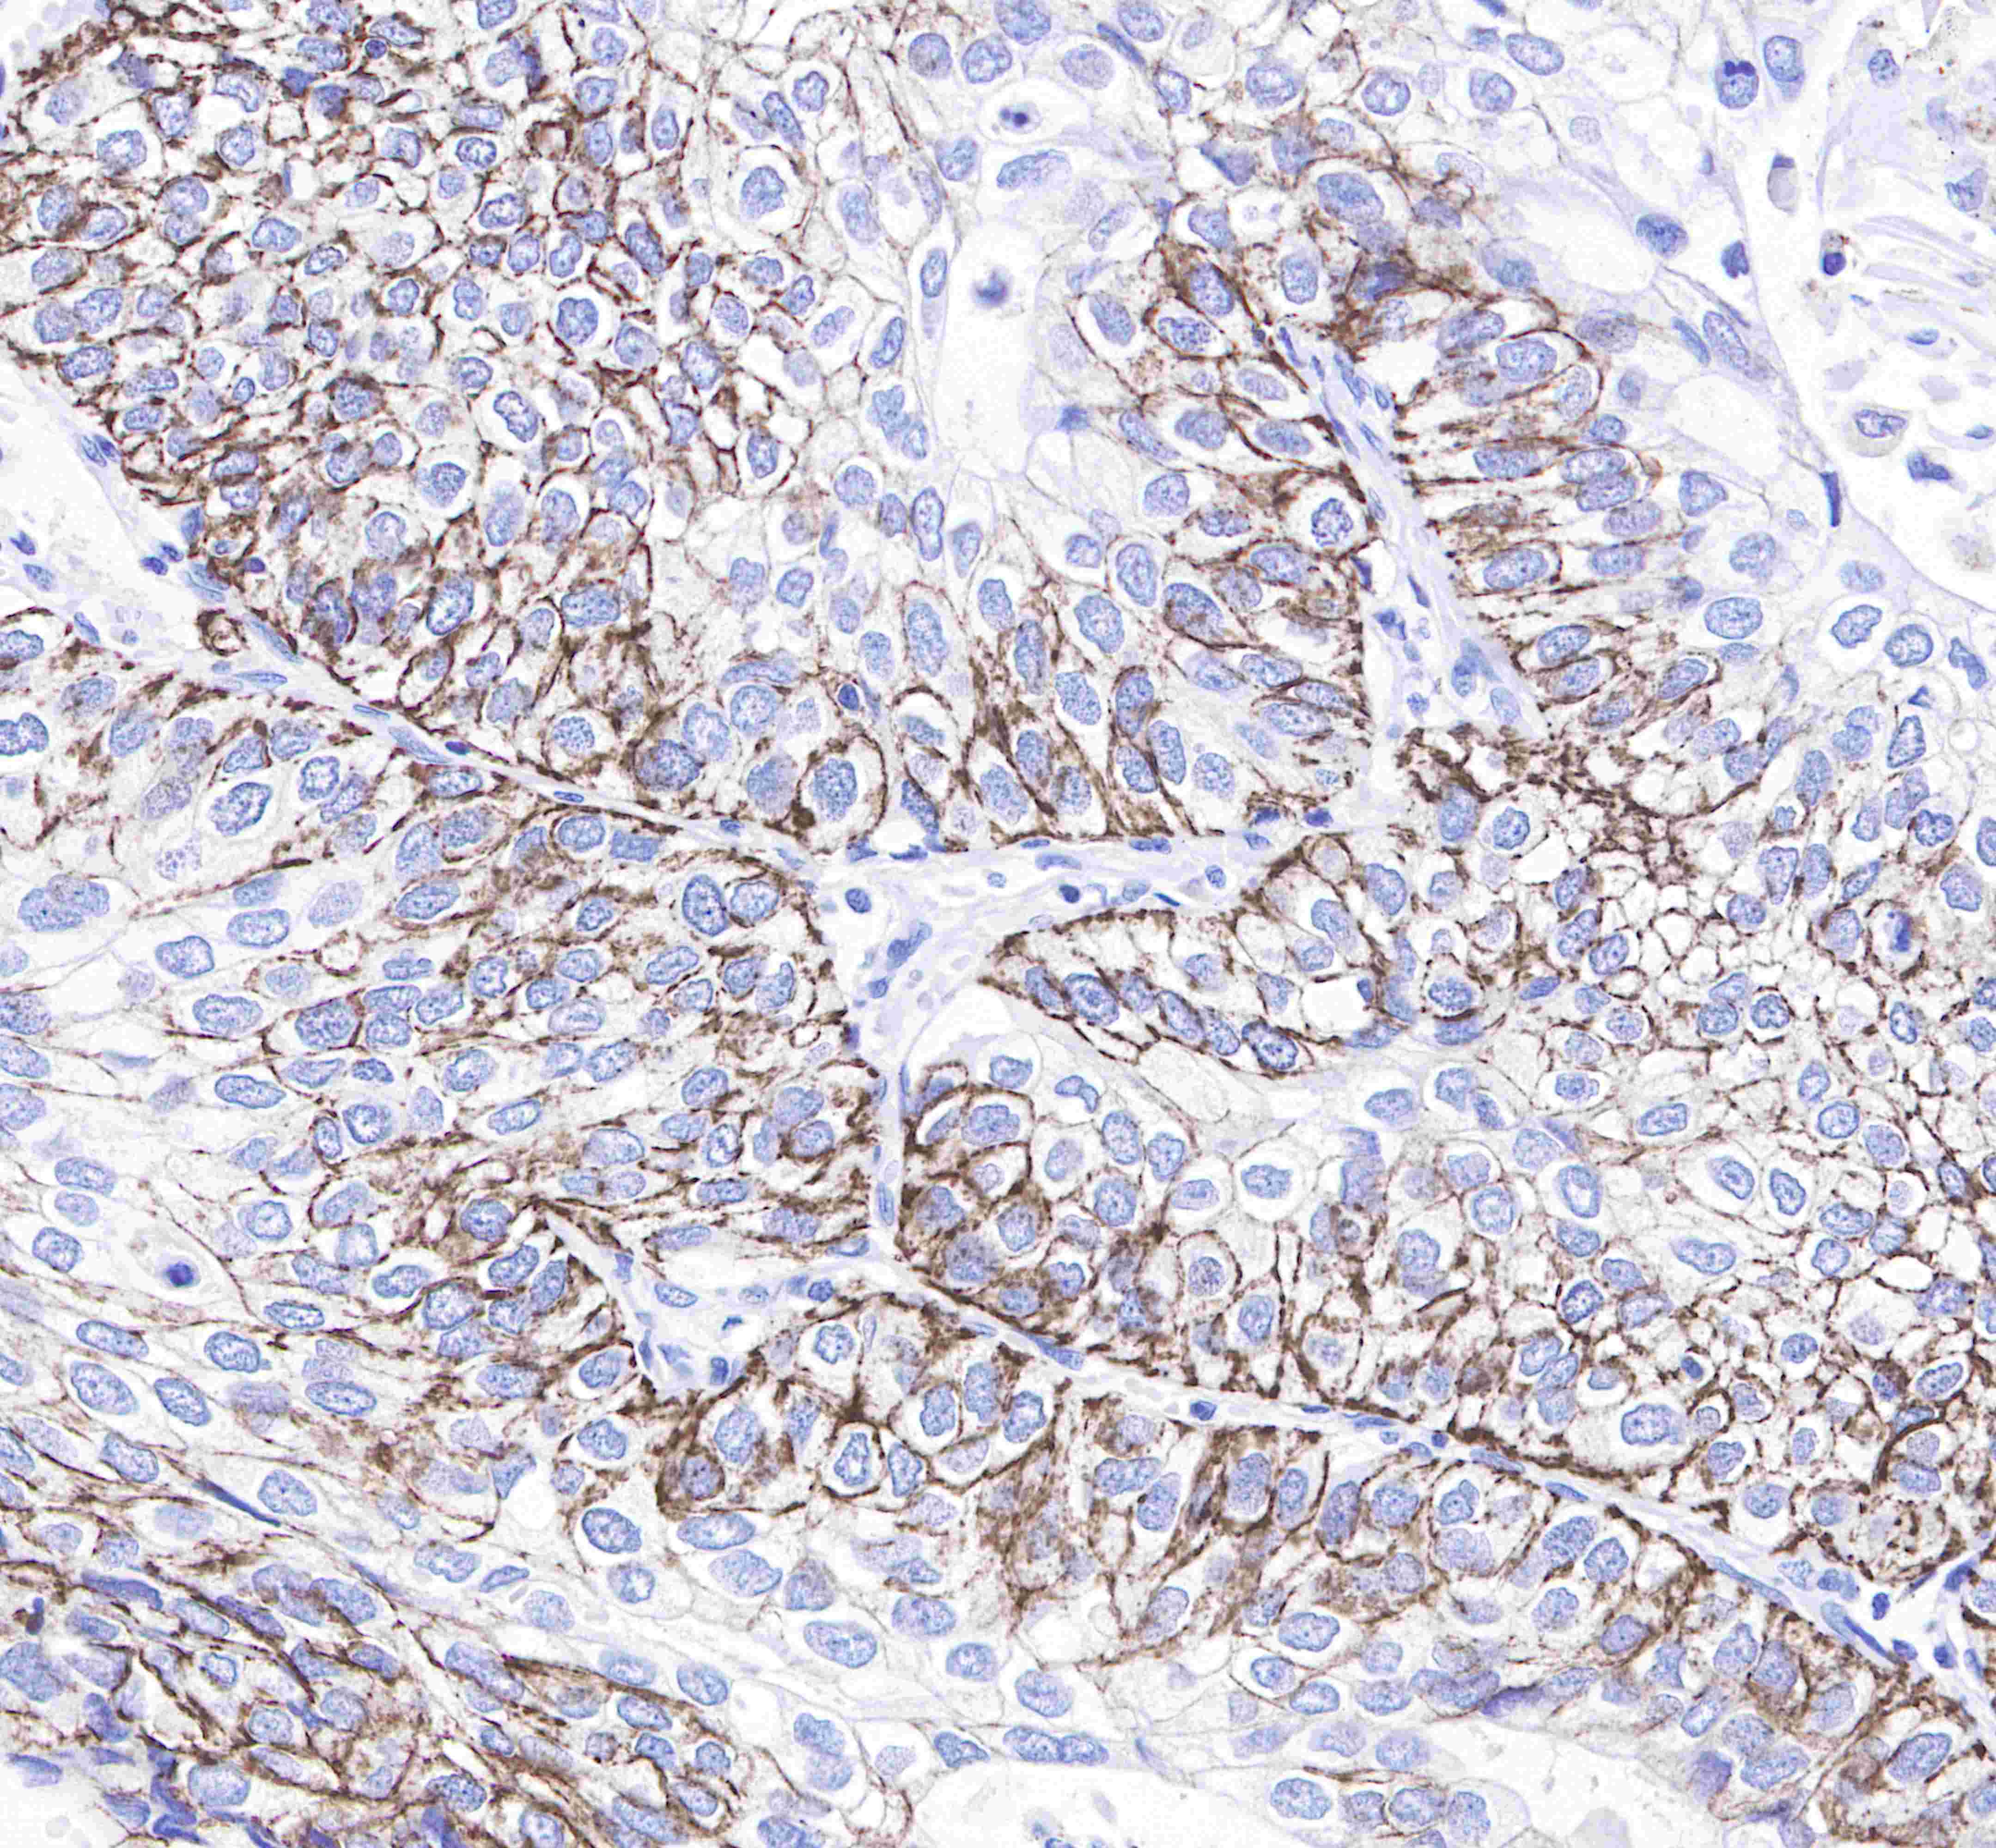

| IHC-P |

1:250 |

Claudin-1 is a protein that in humans is encoded by the CLDN1 gene.It belongs to the group of claudins.

Tight junctions represent one mode of cell-to-cell adhesion in epithelial or endothelial cell sheets, forming continuous seals around cells and serving as a physical barrier to prevent solutes and water from passing freely through the paracellular space. These junctions are composed of sets of continuous networking strands in the outwardly facing cytoplasmic leaflet, with complementary grooves in the inwardly facing extracytoplasmic leaflet. The protein encoded by this gene, a member of the claudin family, is an integral membrane protein and a component of tight junction strands. Loss of function mutations result in neonatal ichthyosis-sclerosing cholangitis syndrome.